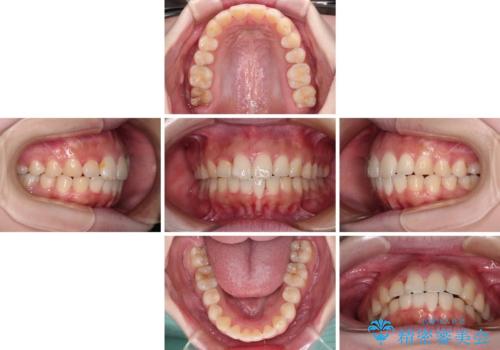

前歯のデコボコをインビザラインできれいに整える

前歯の捻れを改善するとともに、口元が少しでも引っ込むように治療計画を立て、仕上げることができました。

- 2年6ヶ月